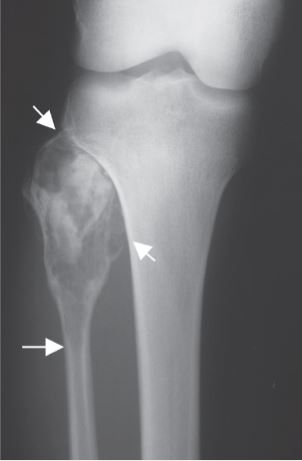

A fibular resection is a procedure that involves removing a tumor, usually malignant or benign aggressive, of the fibula. The fibula is the bone that is next to your shin bone. This is done while preserving the surrounding bone and soft tissues.